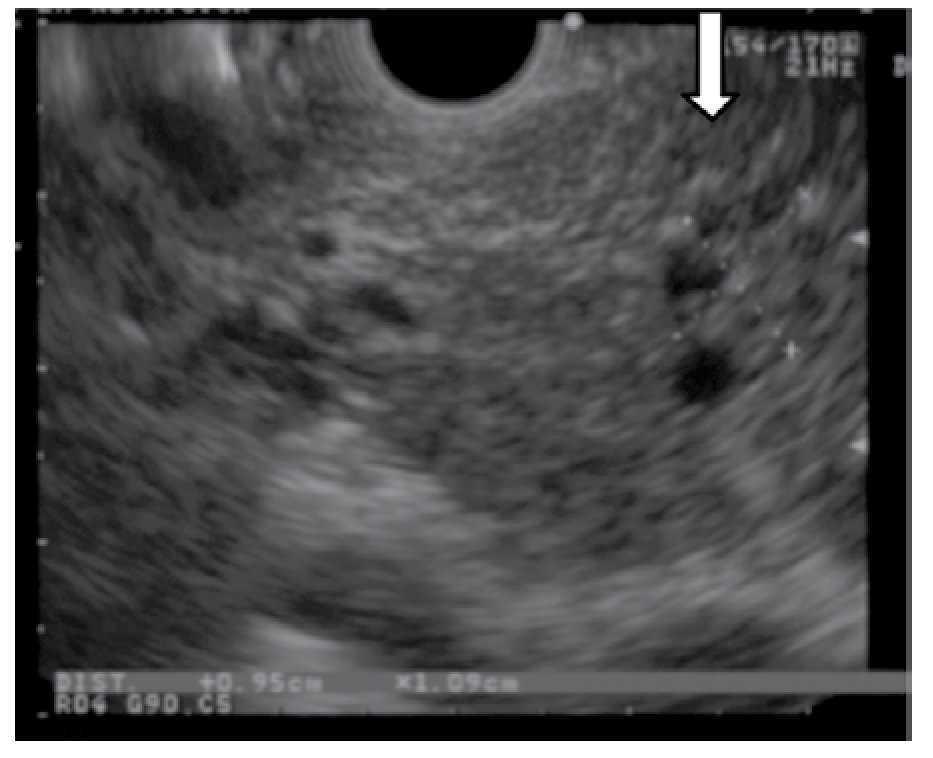

Magnetic resonance cholangiopancreatography (MRCP) showed a stellar image in the pancreatic neck with a normal main pancreatic duct (Figure 1). The endoscopic ultrasound (EUS) showed a small multicystic area of 10 x 9 mm in size with septa connected through a side branch with the main pancreatic duct without solid component or lymphadenopathy; the diagnosis of side branch IPMN was suggested (Figure 2). Patient underwent to pancreatoduodenectomy and the pathology reported a sidebranch duct IPMN, with pancreatic intraepithelial neoplasia type 2 (PanIN-2) (Figures 3 and 4). Since the surgery, patient has recovered well and is asymptomatic after eighteen months of follow-up.

○ Figure 2. Linear EUS that shows a small multicystic lesion with septa in the neck of the pancreas (white arrow) connected through a side branch with the main pancreatic duct.